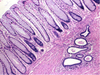

What process is occurring in this endometrium?

A

What process is occurring in this endometrium?

A